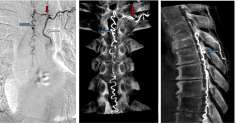

• Spinal Dural Arteriovenous Fistulas (Type I)

• CT scan of Type I Spinal Dural Arteriovenous Fistula

Figure 1. Type I Spinal Dural Arteriovenous Fistula - Spinal angiogram (left image) of a left sided spinal segmental artery (white arrow) with an abnormal connection (red arrow) to a spinal cord vein that has become abnormally enlarged (blue arrow)

• These malformations represent 70% of spinal vascular malformations and are the result of an abnormal connection forming between an artery and a vein in the spinal canal dural covering (Figure 1). This connection allows high pressure arterial blood to escape into the low-pressure network of spinal cord veins. Over time, the spinal cord is damaged by the elevated pressure in the veins. Spinal dural arteriovenous fistulas (AVFs) are thought to form spontaneously during adulthood and are not congenital or hereditary. These lesions rarely rupture or bleed, but they do cause significant spinal cord dysfunction that can result in leg weakness, lower body numbness, imbalance, and urinary problems. These malformations are good candidates for surgical treatment and endovascular treatment, which are typically curative.